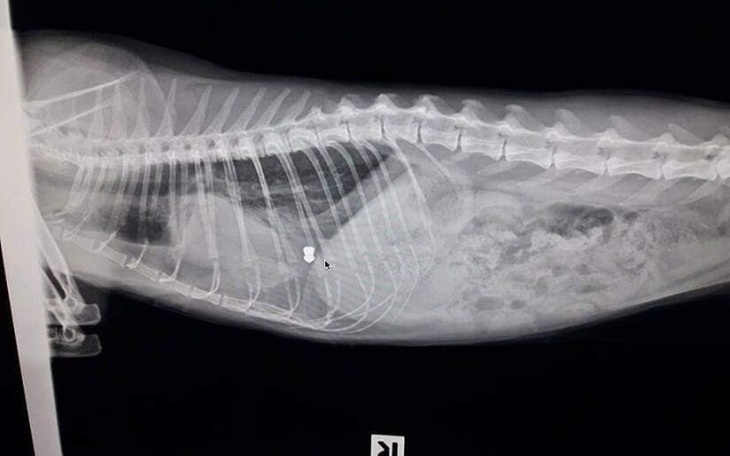

Zgadłbyś, że jest to śrut?? Przyszłoby Ci do głowy, że ktoś zrobił sobie z tego kota żywą tarczę??

Szisza to młoda i nadal bardzo ufna koteczka. Jej płuco to ruina. Pocisk doszczętnie je rozszarpał i utknął głeboko. Śrut wrósł w kocie ciało powodując ból przy każdym najmniejszym oddechu. Płuco Sziszy to pozrastany i zapadnięty twór, który nie spełnia już swojej funkcji.

Konieczny jest jak najszybszy zabieg na otwartej klatce piersiowej. Podczas operacji usunięte zostać powinno całe płuco lub jego płat.